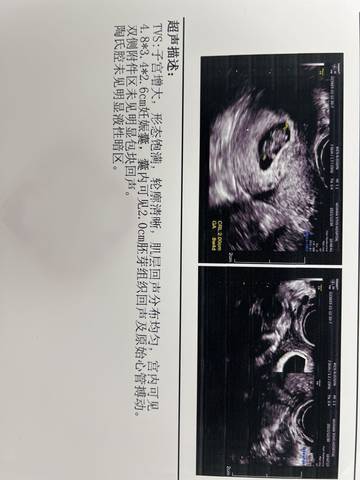

八周五天的B超,看看是男宝还是女宝呀?哈哈哈

journal_insert_pic_1688823005journal_insert_pic_1688823084journal_insert_pic_1688823112journal_insert_pic_1688823173